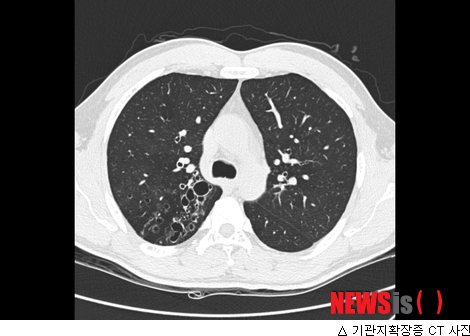

기관지 확장증, 주요 증상과 치료 방법 총정리

기관지 확장증은 기관지의 비정상적인 확장을 의미하며, 이를 경험하는 환자들은 주로 가래, 기침, 호흡 곤란 등의 증상을 겪게 됩니다. 이러한 증상들은 일상생활에 큰 영향을 미칠 수 있으며, 질병의 원인과 치료 방법에 대한 체계적인 이해가 더욱 필요합니다. 이번 포스트에서는 기관지 확장증의 주요 증상과 치료 방법을 총정리하겠습니다. 살면서 알레르기나 감기와 같은 사소한 건강 문제를 겪으면서도, 내 몸의 변화에 대한 소홀함이 후에 큰 문제가 될 수 있음을 잊지 말아야 합니다.